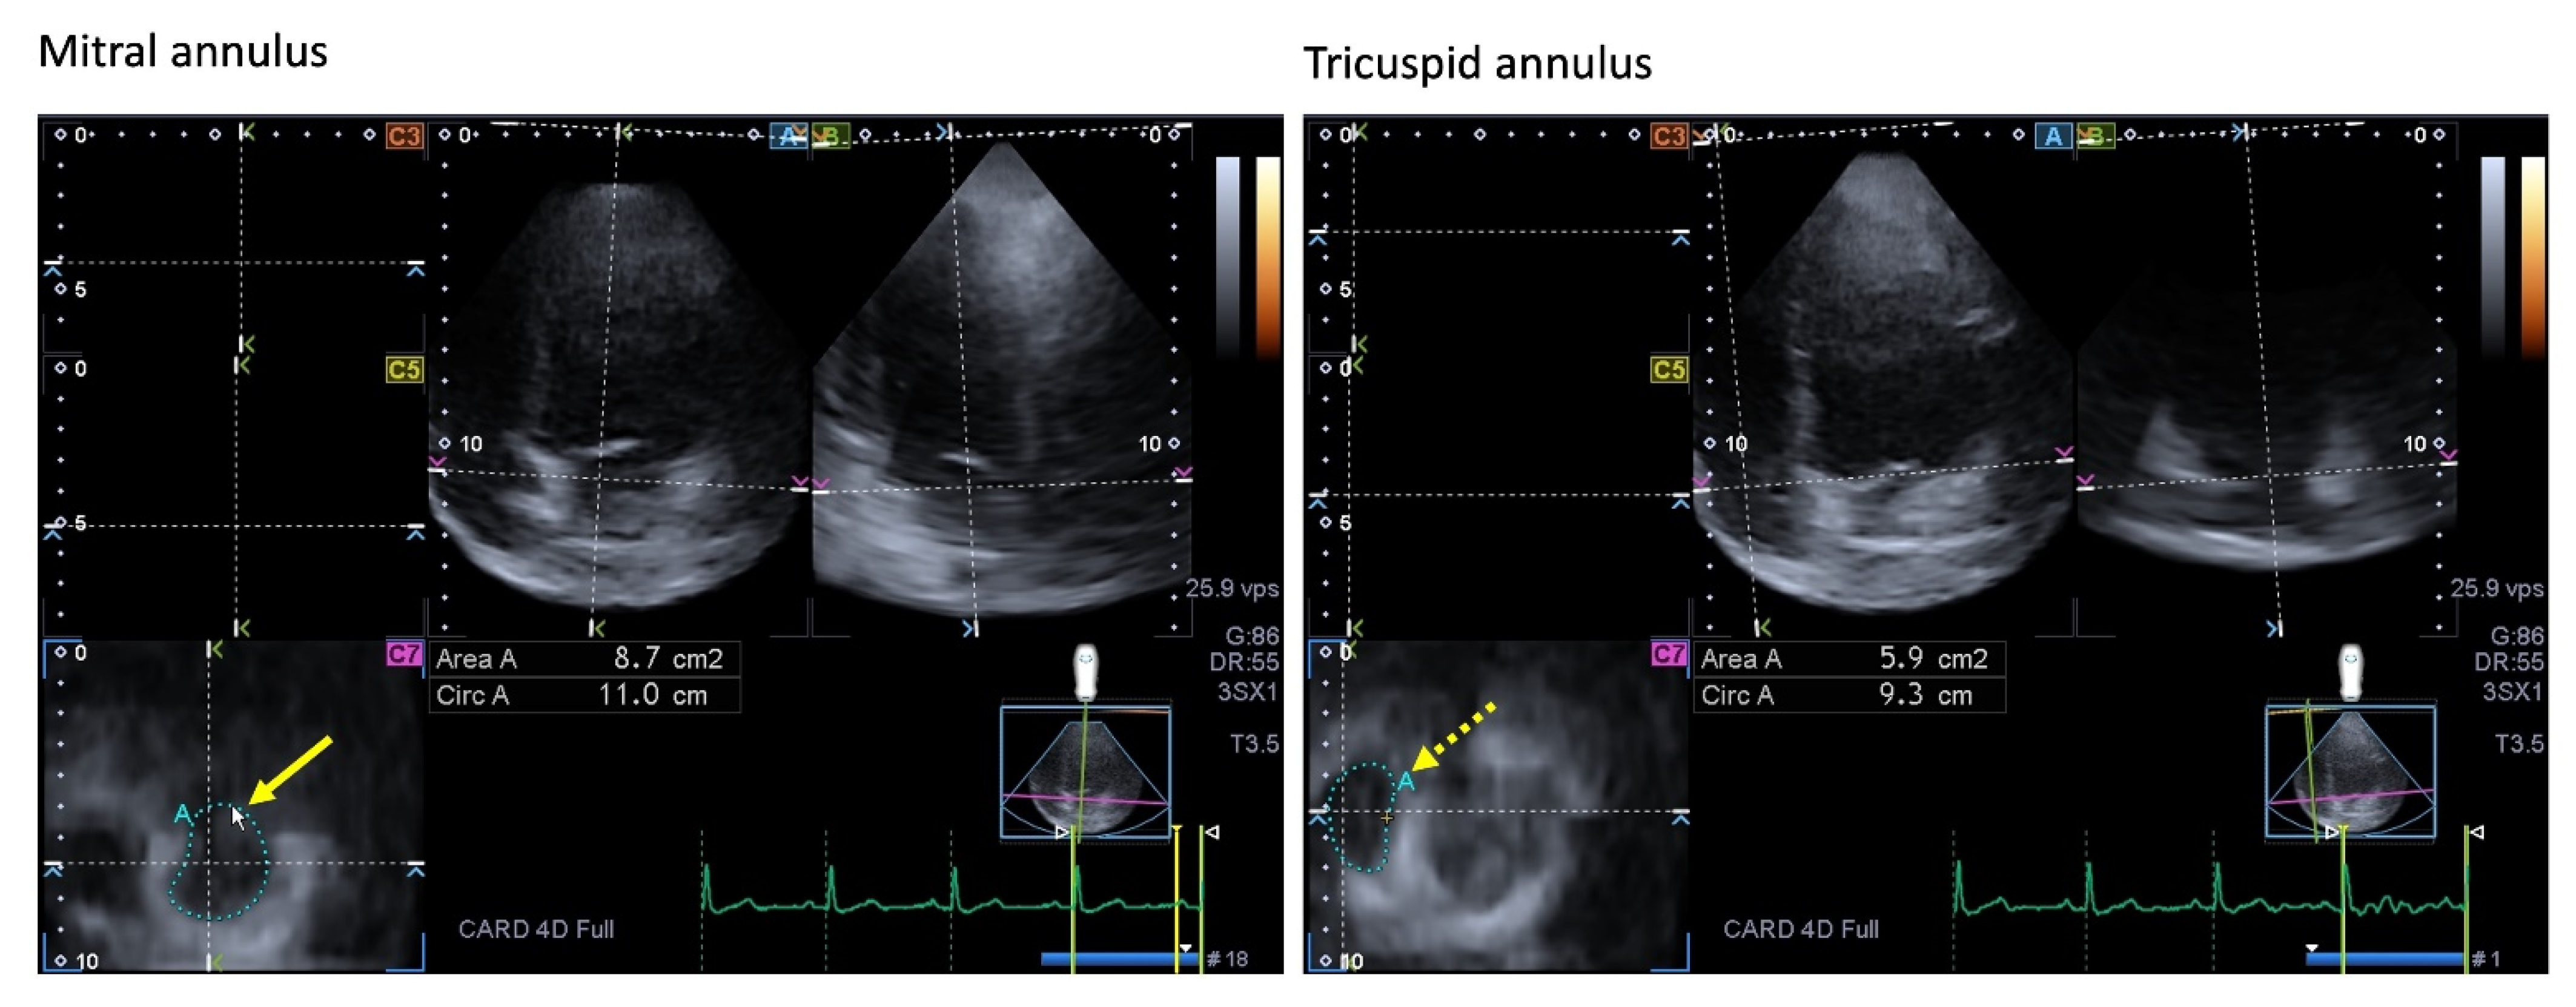

| Mitral valve | MA was dilated and functionally impaired. | [87] | 20 |

| Tricuspid valve | TA was dilated, with preserved sphincter-like function. | [18] * | 21 |